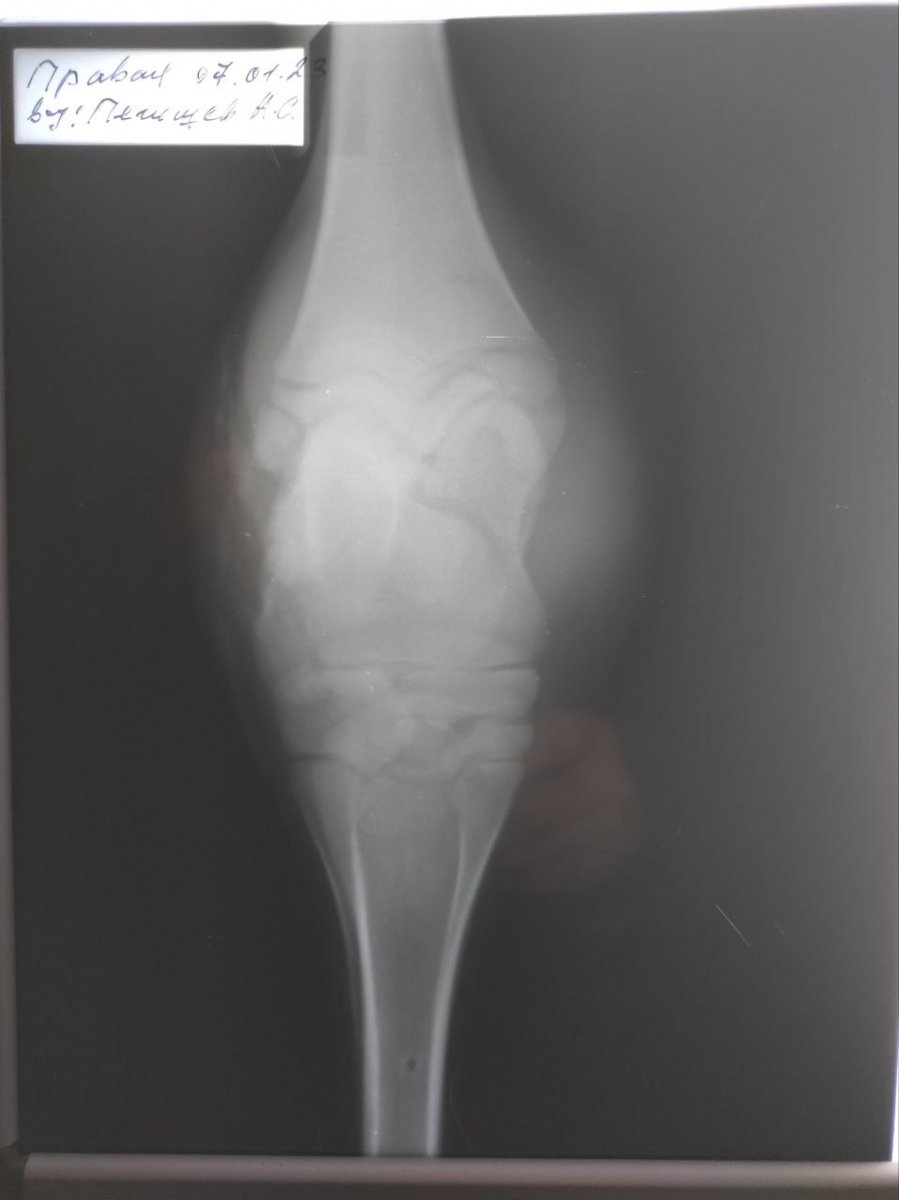

1,2 фото - нога на момент первого осмотра, 3,4 фото - на 8-ой день лечения, 5 - тот самый свищ, 6,7,8,9 - рентген перед лечением